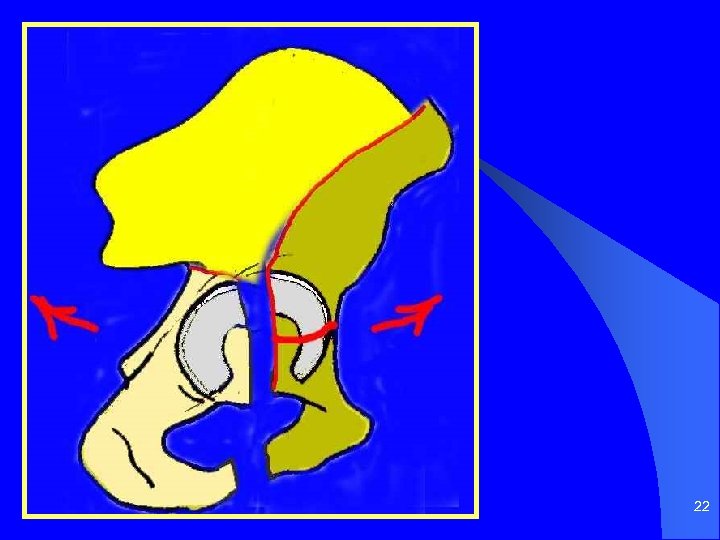

21

22